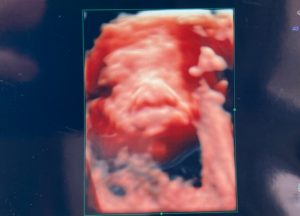

エコー写真

横顔^^ベッピンさんね~(笑)

残念ながら、お顔はやはり見えず・・・

先生が頑張って写そうとしてくれた結果

こんな感じで撮ってくれました!

綺麗に写ってないけど・・・って渡されましたが

十分です先生、ありがとうございます。って感じです!